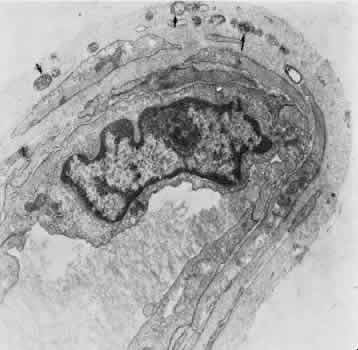

Retinal Arteries and Arterioles The retinal arteries are branches of the superior and inferior papillary arteries. Each papillary artery typically divides again on the surface of the optic disc to form temporal and nasal branches. The anatomical division of the retinal arteries into superior and inferior halves is usually maintained throughout the retina because vessels normally rarely cross the horizontal raphe. The major branch arteries are about 120 μm in diameter and course within the nerve fiber layer and ganglion cell layer of the retina. They are smaller in diameter and straighter in course than their accompanying draining veins. Subsequent division of the arteries results in a decrease in the caliber of the vessel. The branching is of two types: dichotomous and side-arm. Trifur-cations are extremely rare. Dichotomous branches involve two similar-sized trunks splitting from a larger trunk. Smaller vessels arising from dichotomous branches course toward the periphery of the retina, becoming arterioles that supply the retina anterior to the equator. Side-arm branches are small precapillary arterioles branching from a larger vessel to supply blood to the local capillary system. In the posterior retina, the fine arterioles that arise by side-arm branching leave the main arteries and enter the inner plexiform and ganglion cell layers. Only capillaries are found as deep as the inner nuclear layer, however. The blood column within retinal arterioles is visible with a direct ophthalmoscope down to the third-order branches. Normally, the walls of the vessels themselves are transparent to direct observation; it is the blood column that makes the vessels visible on ophthalmoscopy. The intima of the retinal arteries contains a single layer of endothelial cells surrounded by a basement membrane. Collagen fibrils may be seen in the basement membrane. Elastic fibrils are not present, and there is no internal elastic membrane. The media of the major vessels near the disc contains five to seven layers of circularly arranged smooth muscle cells. These cells contain well-developed myofilaments and dense bodies and are surrounded by a thick and often lamellated basement membrane containing collagen fibers. Collagen types 1, 2, 4, and 5, laminin, heparin sulfate proteoglycan core protein, and fibronectin all have been identified as components of the basement membrane.12 The basement membrane surrounding the innermost layer of the smooth muscle cells is continuous with the basement membrane surrounding the endothelial cells. Some areas exhibit a thinning of this membrane, and in these areas the membranes of the endothelial cell and smooth muscle cell are closely apposed. The basement membrane surrounding the outermost layers of smooth muscle cells contains increasing amounts of collagen and tends to become vacuolated and to accumulate debris with aging. As the major retinal arteries branch and approach the equator of the eye, the media becomes less well developed and contains approximately two layers of smooth muscle cells. At this point and further peripherally, the retinal vessels should be referred to as arterioles. The adventitia consists of collagenous connective tissue that is continuous with the basement membrane surrounding the outer layers of smooth muscle cells of the media. A smooth muscle cell may occasionally be displaced into the adventitia. Glial cells are in direct contact with the adventitia. No nerve fibers have been found in the media or adventitia of human retinal arteries or arterioles.13 Although the ophthalmic artery contains sympathetic nerve fiber endings and is therefore under control of the autonomic nervous system, there is apparently no central regulation of the blood flow in the retina itself. Evidence implies that some species may have autonomic innervation of the preretinal blood vessels, however.14 Retinal arterioles are similar to the arteries except that the lumen is small (8 to 15 μm in diameter), the media contains one or two layers of circularly or obliquely arranged smooth muscle cells, and the adventitia is poorly developed and consists of the outermost layer of basement membrane surrounding the smooth muscle cells and small amounts of collagen fibrils (Fig. 4).15